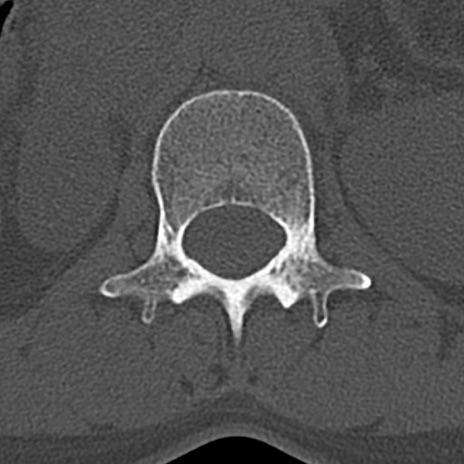

【整形】TIPS症例4 腰椎CT(横断像)

腰椎CT

横断像と矢状断像